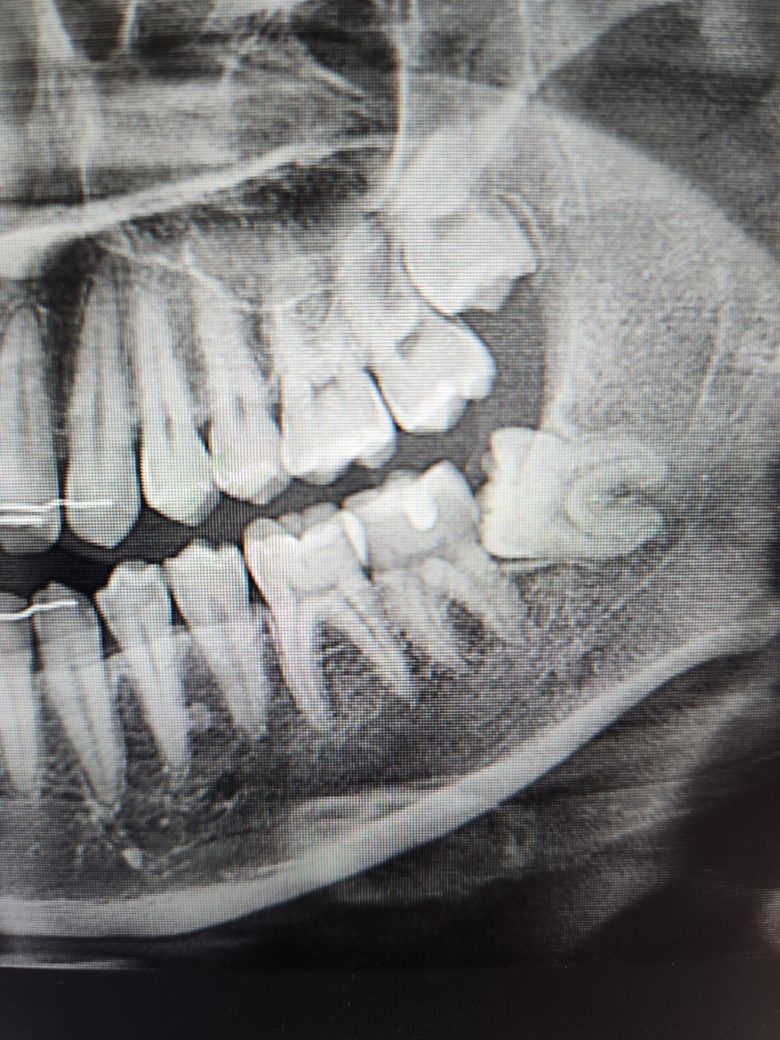

하악 38번 발치한지 10일차인데 첫주에는 별 증상 없다가 9일차부터 37번부터 그 주변 잇몸, 턱, 볼이 너무 아팠습니다. 시린거야 구멍 뚫려있으니까 그렇다 치는데 진짜 자다 깨고 두통이 올 정도로 아팠어요. 그래서 10일차인 오늘 발치한 치과가 아닌 일반 치과에 방문했는데 의사쌤이 37번 뿌리가 많이 노출되어 있다면서 익스플로러로 37번 콱 찍어보니까 진짜 자지러질정도로 아팠습니다. 의사쌤이 이정도 반응이면 아래 염증이 있는걸 수도 있다고 신경치료가 필요할 수도 있다고 하셔서 다른 보존전문쌤이 오셔서 엑스레이 찍었는데 엑스레이 상으로는 조금 애매하고 이걸 신경치료하긴 조금 치아가 아까우니 소염제랑 항생제 먹으면서 조금 지켜보자더군요. 제가 충치 있냐고 하니까 충치도 없어보인다고 하시구요. 발치할 때 염증반응도 없었는데 발치하고 나서 옆 치아에 염증이 생길 수 있나요? ㅠㅠ… 신경치료는 진짜 하기 싫은데 ㅠㅠ.. 시간이 지나면 통증이 좀 없어질까요? ㅠ 사진은 뽑기 전 사진이에요

사진을 보면 사랑니 빼고 나서 사랑니 앞쪽 치아 아래쪽에 충치가 생겨서 그럴가능성이 있어 보입니다. 저 부위에 충치가 생기면 신경치료를 해야될 가능성이 있습니다.

1. 사랑니가 부분매복으로 옆으로 누워있었기 때문에 아무래도 옆의 치아(37번)에 영향(치근흡수, 충치)을 주고 있었을 가능성도 있습니다.

2. 저 사진상에서는 38번과 37번 뿌리끝 염증이 약간 존재하고 있던 것으로 보여집니다.

3. 익스플로러로 37번 치아 주위를 확인(탐침)해봤을 때 상당히 찌릿한 느낌이 들었다면 치아에 금이 갔을 확률도 있습니다.

4. 일단은 진통제로 통증 조절을 좀 해보시고 그래도 계속해서 아프다면 치과에 뽑기 전 사진(원본)도 같이 가져가서 상담을 받아보시면 좋을 것 같습니다. 뽑은 뒤의 파노라마 사진상으로는 발치와(발치공간) 빈공간이 남아 있기 때문에 원래 뽑기 전 38번에 염증이 존재했었다는걸 알기 어렵습니다. 뿌리끝 염증이 있는 치아 발치 후에는 보통 염증 제거 및 소파술을 더 철저히 해줍니다.